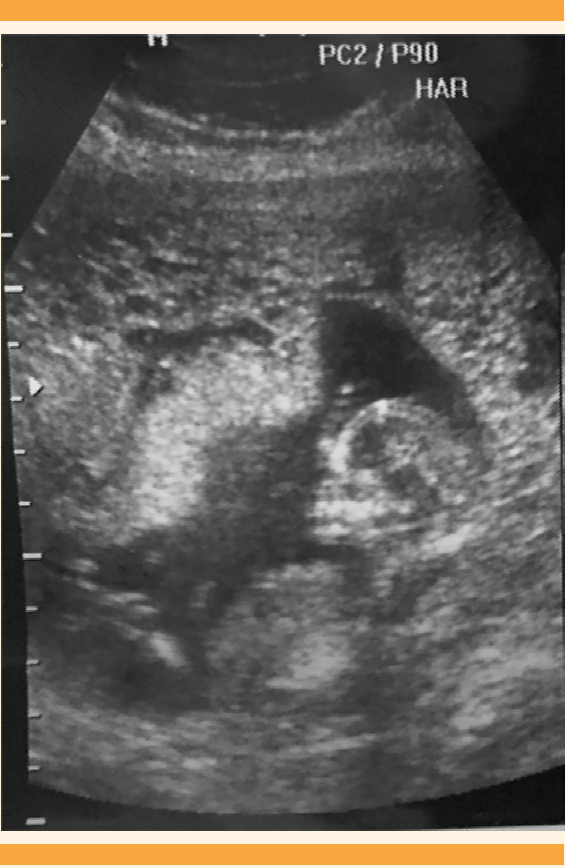

Figura 4 Ultrasonido abdomino-pélvico del segundo trimestre del embarazo (Caso 2). Placenta heterogénea, con de múltiples quistes focalizados hacia el fondo uterino, y feto único vivo.

Caso 2. Paciente de 27 años de edad, con antecedentes ginecoobstétricos de tres embarazos y dos partos de término. El embarazo en curso estaba en las 25.4 semanas, por fecha de la última menstruación, con episodios de amenaza de aborto desde el primer trimestre e infección recurrente de vías urinarias. Se hospitalizó debido a la persistencia de cefalea, palpitaciones, insomnio, desesperación y sudoración profusa. Al ingreso hospitalario la paciente se encontró: consciente, tensión arterial de 150-100 mmHg, frecuencia cardiaca de 108 latidos por minuto y temperatura de 37°C. Antecedentes obstétricos: embarazo de 26 semanas, por fecha de la última menstruación, con feto único vivo, intrauterino, sin alteraciones morfológicas, sin trabajo de parto, cuello uterino cerrado y escasa hemorragia transvaginal. La frecuencia cardiaca fetal: 110 lpm, peso fetal estimado 710 g, ILA de 18, placenta con inserción baja, en la cara anterior del segmento uterino, con imágenes “en esponja” focalizadas, con engrosamiento anormal de 10 cm en un extremo y hacia el fondo uterino, placenta normal con grosor de 3.7 cm, ovarios con imágenes quísticas mayores de 10 cm, edad gestacional 24.1 semanas por fetometría (Figura 4).

El caso 2 correspondió a mola parcial o incompleta con feto vivo (Figura 4), que cursó clínicamente de manera atípica. La bibliografía reporta que rara vez se asocia con complicaciones médicas y casi siempre la hCG es menor de 100,000 mUI/mL.22 En este caso se asoció con hiperemesis, hipertiroidismo, preeclampsia severa, placenta previa y β-hCG de 482,174 mUI/mL. Además, el feto no tuvo malformaciones congénitas mayores, aunque no se confirmó o descartó triploidia porque no fue posible obtener el cariotipo. Lembet y sus colaboradores23 reportaron un caso semejante con feto vivo de 560 g, que no sobrevivió a los cuidados neonatales intensivos, el cariotipo del feto y la placenta fue 46XY. Está reportado que 32% de los casos de mola parcial pueden tener cariotipos normales.24 En el caso aquí comunicado el diagnóstico temprano de mola incompleta se derivó del estudio temprano del ultrasonido pélvico-abdominal del primer trimestre del embarazo, que mostró imágenes focalizadas de “placenta quística”, sugerentes de mola hidatiforme parcial, además de concentraciones séricas de hCG mayores de 100,000 mUI/mL. El estudio histopatológico confirmó dos tipos de vellosidades (Figura 5). Desde el punto de vista histológico y biológico todo lo anterior cumplió los criterios de mola parcial, que es la mezcla en la misma placenta de vellosidades normales y vellosidades hidrópicas, pero sin hiperplasia del trofoblasto (Figura 6). Estos hallazgos deberían complementarse con una biopsia de las vellosidades coriales o una amniocentesis, para evaluar el cariotipo y normar la decisión clínica.